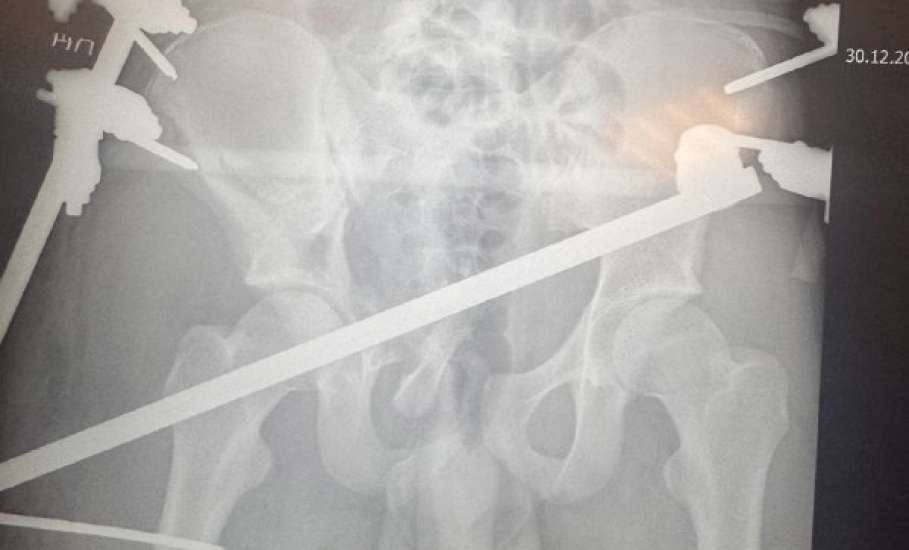

У парня диагностировали многооскольчатый перелом таза, массивную забрюшинную гематому, повреждения внутренних органов и закрытую черепно-мозговую травму. Ситуация осложнялась развивающимся травматическим шоком.

Для остеосинтеза был использован современный рентгеннегативный аппарат внешней фиксации, позволяющий с высокой точностью сопоставить осколки.